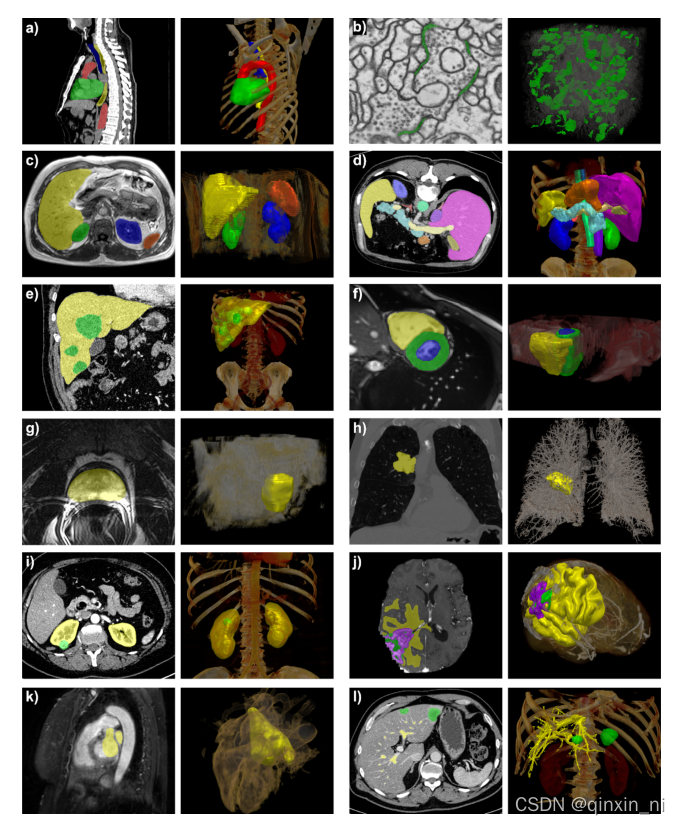

nnUNet是一个不需要任何实验设计和参数调节就可以为你训练3D医学图像的深度学习语义分割框架。一些对于比较典型的数据集的分割效果在下中展示。

1.nnUNet掌握了数据集的多样性和标签的属性: 以上所有的测试集都来自nnUNet对国际上各项挑战赛事的数据集的应用,左边是原数据的标签,右边是nnUNet模型的推理结果。所有这些可视化操作是在MITK上进行的。